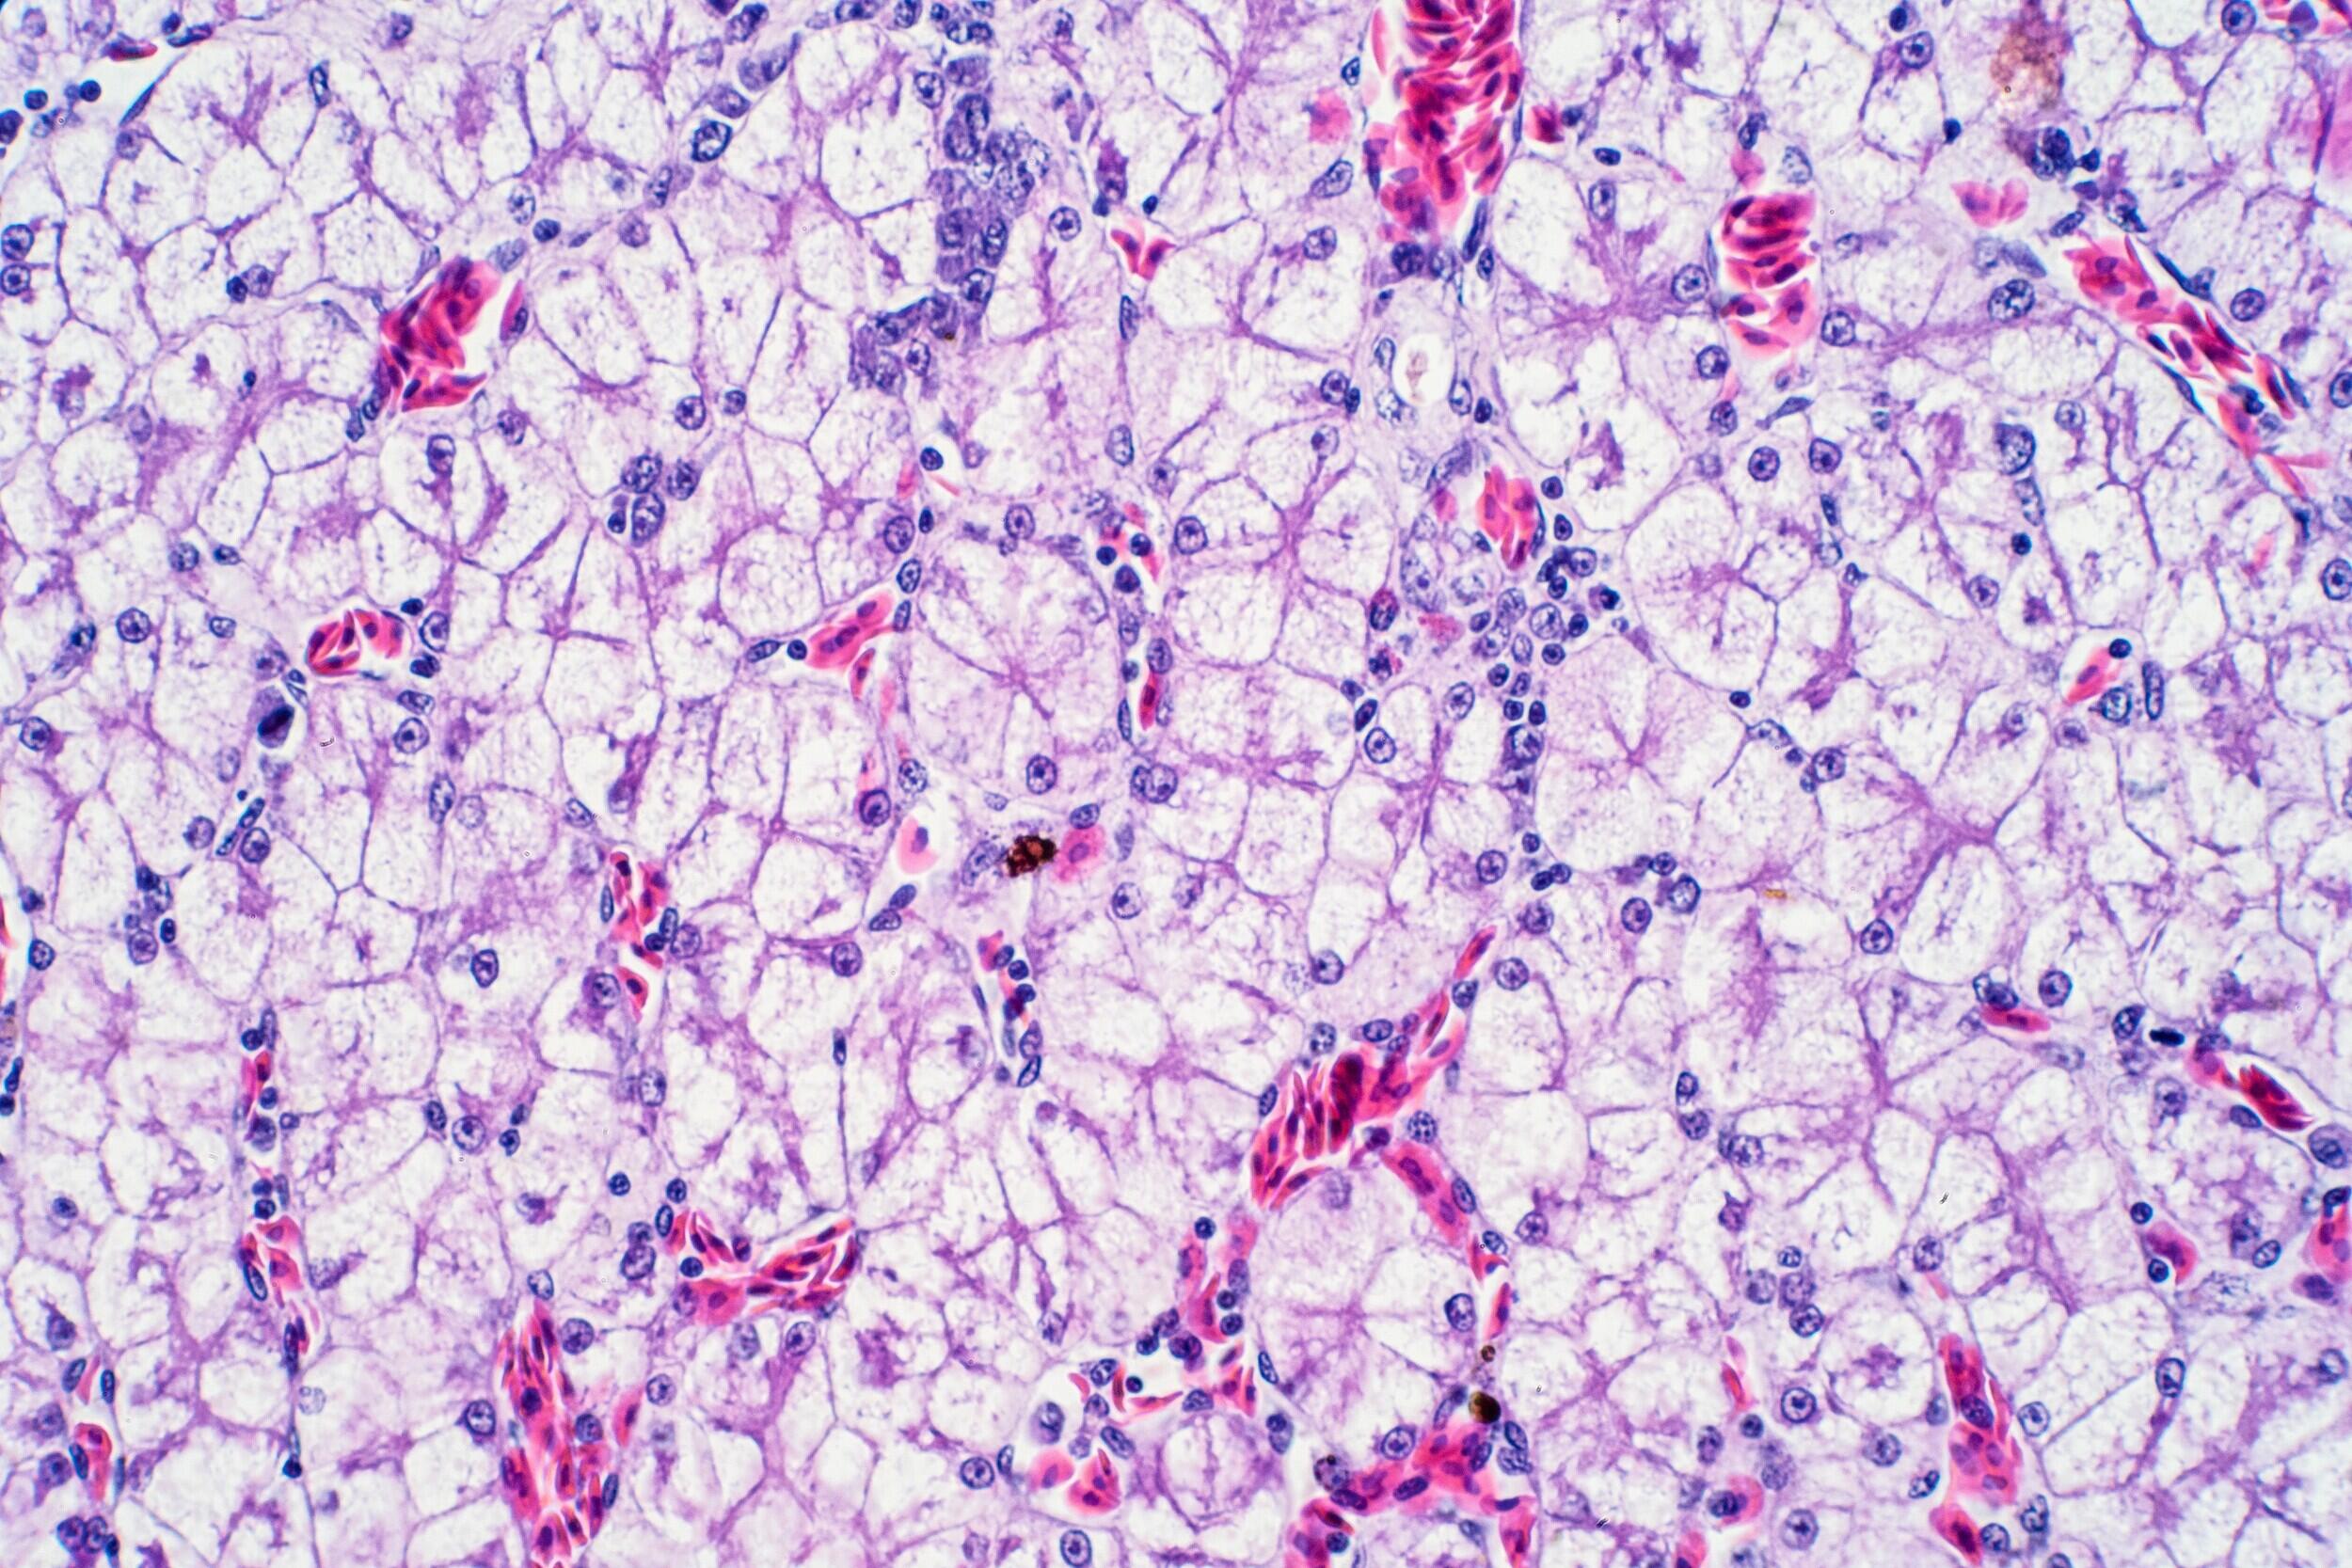

The LINC complex — a group of proteins known as the nuclear linker of nucleoskeleton to cytoskeleton — anchors the nucleus to the cell. The study, using 3D culture models of cell clusters known as acini, suggests that mechanically disrupting the LINC complex destabilizes the clusters.

“If these main connections that help anchor the nucleus are disrupted, the cells try their best to compensate in order to keep things normal,” said Vani Narayanan, a doctoral candidate in the Department of Biomedical Engineering in the VCU College of Engineering and lead co-author of the study. “Unfortunately, this compensation becomes over-compensation. Various proteins that should ideally remain in nominal amounts within the cell for proper cellular function get unregulated, causing rapid movement of cells within the acinus, abnormal cell division and migration and, hence, the system collapses.”

Problems with cells such as epithelial cells — which separate the body from the outside environment and provide barriers between different areas inside organs, such as the liver, and are critical for tissue and organ function — are linked to defective wound healing and the development and progression of diseases such as cancer.

“The mechanics of the cells affect how tissue structures form,” said Daniel Conway, Ph.D., associate professor in the Department of Biomedical Engineering and co-author of the study. “If you change the mechanical properties of individual cells, they lose the ability to form more complex tissue or to stay organized. … The structures actually aren't that stable, [therefore] disruptions in physical connections between or within cells can result in these structures collapsing.”